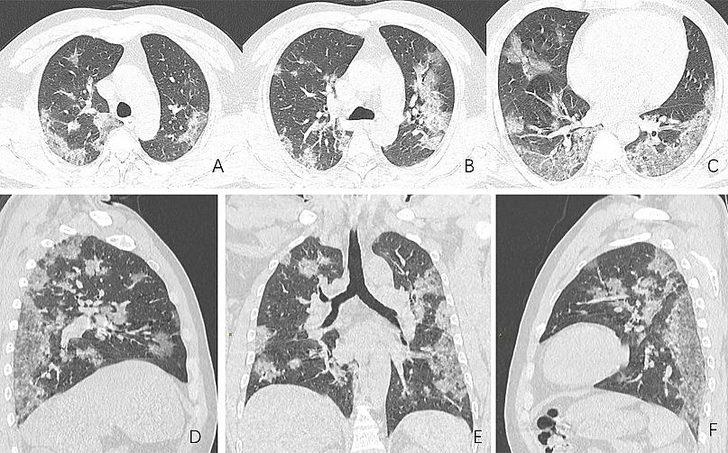

Radyologlar, tomografi görüntüleri sayesinde lezyonların dağılımının daha net anlaşılmasının, virüsü tanıma ve tedavisi için yapılan araştırmalarda önemli olduğunun altını çiziyor.

Covid-19'dan kaynaklı zatürre hastası 54 yaşındaki bir kadının transversal ve koronal bilgisayarlı tomografi (BT) görüntülerinde pulmoner lezyonların üst lobda daha yaygın olduğu görülüyor.